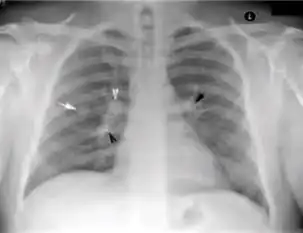

2. Any cavitary lesion - Lucency (darkened area) within the lung parenchyma, with or without irregular margins that might be surrounded by an area of airspace consolidation or infiltrates, or by nodular or fibrotic (reticular) densities, or both. The walls surrounding the lucent area can be thick or thin. Calcification can exist around a cavity.

-

Chest X-ray of a person with advanced tuberculosis: Infection in both lungs is marked by white arrow-heads, and the formation of a cavity is marked by black arrows.